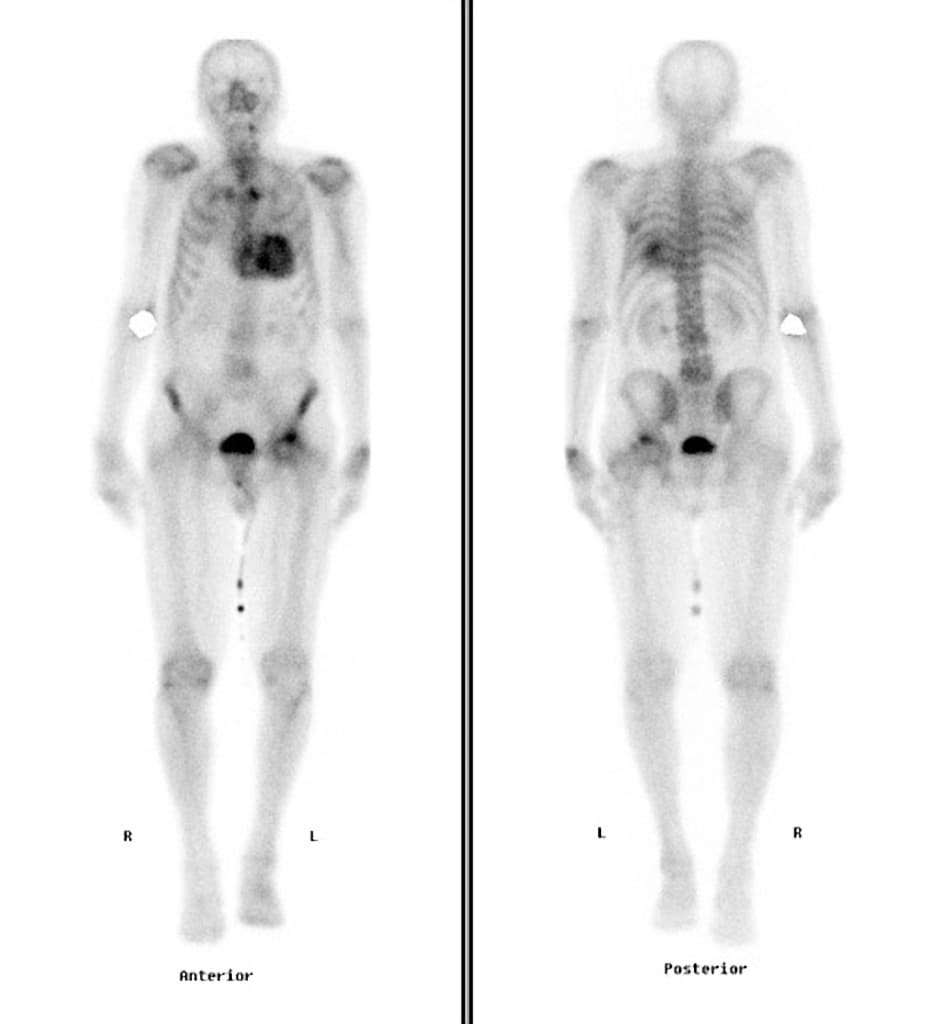

- Tiên lượng (prognosis) ở dạng đỉnh thất (apical pattern) này có thể xấu hơn do tăng tần suất các biến cố tim mạch bất lợi (increased incidence of adverse cardiac events).

Bệnh cơ tim phì đại - dạng đỉnh thất với tắc nghẽn ở đoạn giữa thất (Hypertrophic cardiomyopathy - apical pattern with midventricular obstruction)

Bệnh cơ tim phì đại dạng đỉnh thất là một thể hình thái riêng biệt của bệnh cơ tim phì đại do bất thường sợi co cơ, chủ yếu ảnh hưởng đến đỉnh thất trái. Khác với thể phì đại vách không đối xứng phổ biến hơn, thể này biểu hiện bằng sự dày lên cô lập ở vùng đỉnh, thường dẫn đến tắc nghẽn đoạn giữa thất và tạo gradient áp lực. Tình trạng căng thẳng huyết động này có thể gây thiếu máu cơ tim vùng đỉnh, hoại tử lớp dưới nội tâm mạc và xơ hóa thành thất dạng ổ, như thấy trên hình ảnh cộng hưởng từ tăng sáng muộn. Sự hiện diện của mô xơ liên quan đến nguy cơ cao hơn về rối loạn nhịp và các biến cố tim bất lợi, làm tiên lượng có thể xấu hơn. Chẩn đoán phân biệt bao gồm nhồi máu cơ tim, bệnh cơ tim do amyloid và sarcoid, nhưng hình ảnh đặc trưng dạng 'bích' trên chụp buồng thất trái và sự vắng mặt của bệnh động mạch vành giúp khẳng định chẩn đoán.